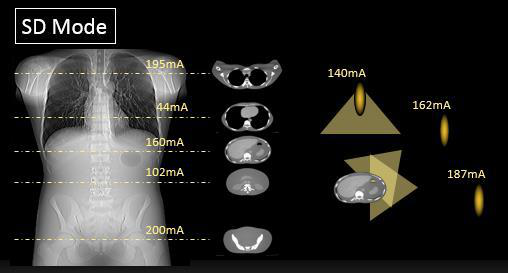

(3)應用 Intelli IP(Advanced)進行高質量的叠代重建

Intell IP(Advanced)是針對低劑量圖像重建算法中的創新,其有效性在以往的用戶中得到了證明。